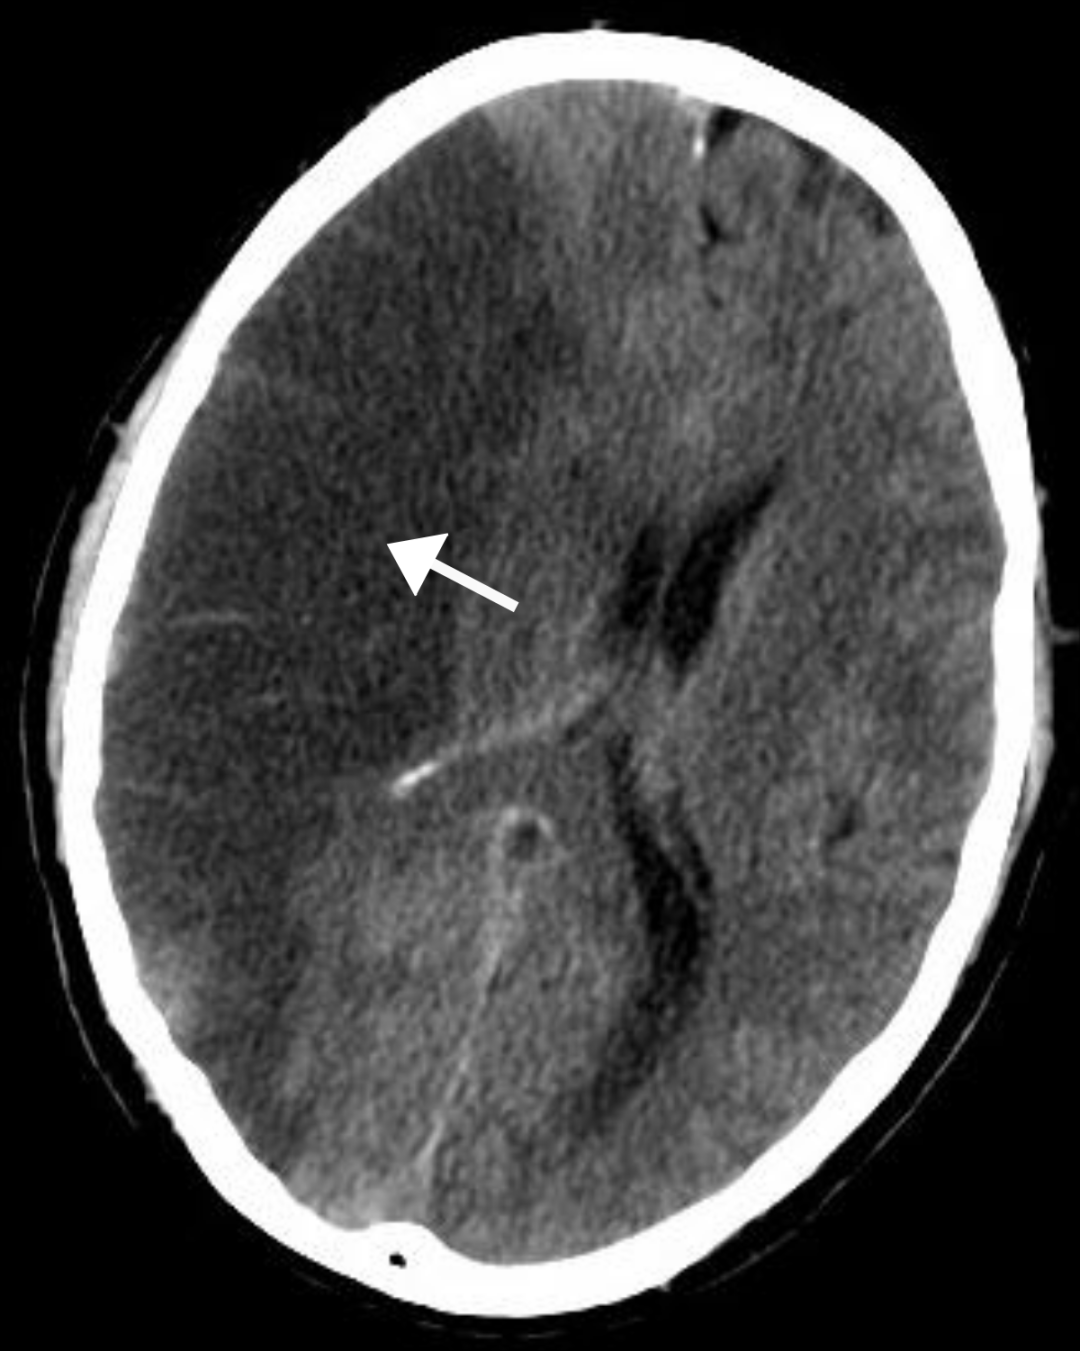

据澳洲媒体报道,一种旨在阻止脑细胞死亡的新型中风药物

名为ARG-007的细胞穿透肽

已经开始在墨尔本进行试验。

中风对于大脑的影响是迅速的,每分钟有190万个脑细胞死亡。

在面临中风患者每分钟百万数量的脑细胞死亡的恐怖情况下,研究人员相信他们的新药ARG-007可能会改变这一现状,有效帮助患者和医疗人员争取到宝贵的治疗时间。

虽然研究仍处于早期阶段,但研究人员表示,他们的临床前研究“一致”表明

他们的药物减少了脑损伤的程度,

而且效果“相当显著”。

“在一项已发表的研究中……

它能够将脑损伤减少70%,

这是相当惊人的,而且脑损伤的减少是持久的。”